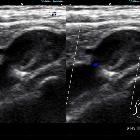

Subclavian

vein aneurysm - Case presentation and discussion. Gray scale and Color Doppler exploration, showing evidence of the patency of the subclavian vein adjacent to the aneurysm.